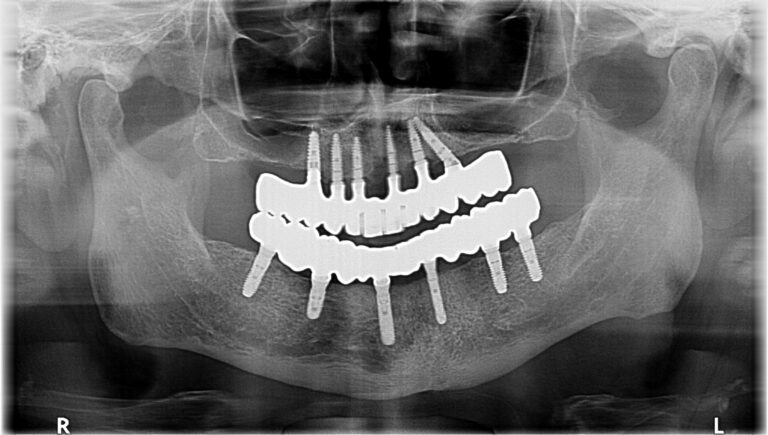

Case 5 – Panos with extreme maxillary atrophy